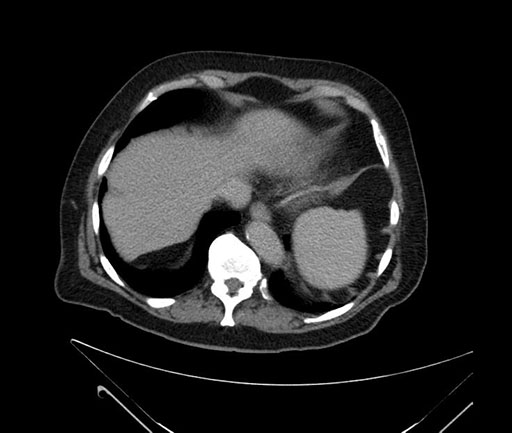

Whipple (pancreaticoduodenectomy) [case 7]

Imaging Analysis

Look through the patient's CT scan to identify any areas of concern for the necessary procedure.

Based on your CT findings, which issue(s) would give reason for "planned slowing down moment(s)" in this case?

Considering a standard Whipple procedure, what step(s) of the operation would you do differently in this case?